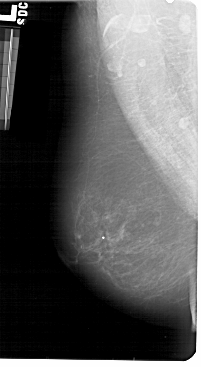

A_1428_1.LEFT_CC

LEFT_MLO LINES 5491 PIXELS_PER_LINE 3001 BITS_PER_PIXEL 12 RESOLUTION 43.5 NON_OVERLAY